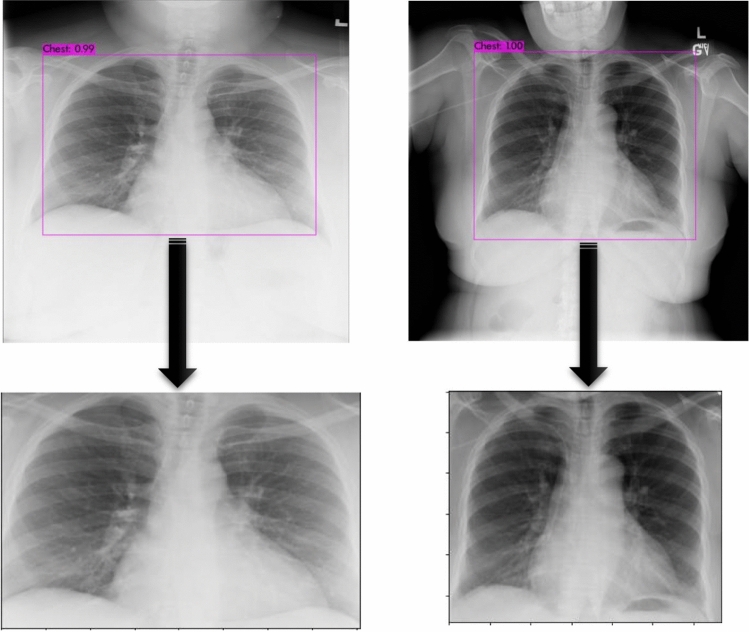

The YOLOv3 detection algorithm is placed at the front of the VGGCOV19-NET and VGG19 models in the Cascade VGGCOV19-NET and Cascade VGG19 models. The YOLOv3 algorithm detects the chest zones in X-ray images and crops them so that a new X-ray data set focusing on the chest zone is attained. This data set is given to the VGGCOV19-NET and VGG19 models as inputs and the training and test processes of the Cascade models are conducted.

Training of the YOLOv3 detection algorithm and automatic cropping of the chest region

YOLOv3 is a deep CNN developed for object detection. The chest region on the chest X-ray image should be tagged before the training of the YOLOv3 model. The labelImg (https://github.com/tzutalin/labelImg) graphical image annotation tool was used for this. A text file was formed for each image using this tool, and the coordinates of the chest region taking place in the image were saved in this file. There are (X0, Y0, X1, Y1) points giving information about the exact location of height (cH), width (cW), and chest region of the images tagged in the text file. The normalization process is conducted to make the formed data set convenient for YOLOv3 architecture. With this process, the center point coordinates (X, Y), height (H), and width (W) data of the chest region tagged in the image are attained as in Eqs. 8 and 9 [54]. These data are shown in Fig. 4.

Processes were conducted with bounding boxes above a certain IoU threshold value while calculating the mAP value to determine the model performance. When the threshold value is taken as 0.50, mAP value for the test data was calculated as 99.80%, and the mean IoU value was calculated as 85.37. These values show that the Chest region was detected with high precision. The weights attained for these performance metrics were saved. Then, all the X-ray images in the data set were given to the trained YOLOv3 algorithm as input and the chest region was automatically detected. The detected chest region was cropped with OpenCv and a new data set containing the chest region was formed. The X-ray images whose Chest region were detected and cropped are shown in Fig. 5.

Fig. 5.

Detection and cropping of the chest region in X-ray images